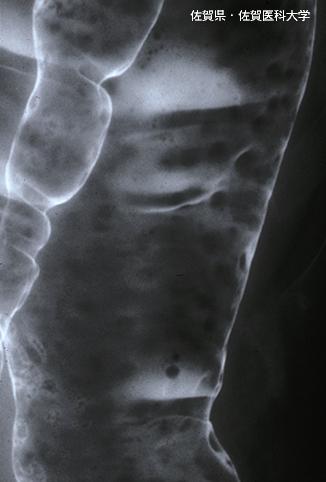

症例提示(所在地,施設名等): 佐賀県・ 佐賀医科大学 (Dr.水口)

疾患(病理主体)の分類悪性リンパ系腫瘍/悪性リンパ腫

部位(臓器別)大腸/下行

検査方法X-P

病変の最大径(ミリ)1〜9

多発腫瘍(同一臓器)有(同時性)